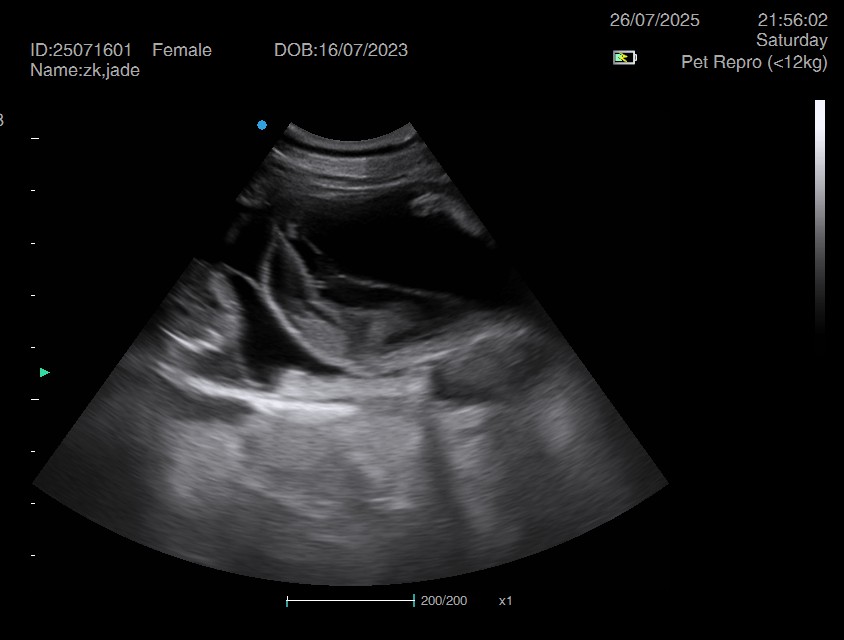

Ultrasound pregnancy scanning is a safe, non-invasive way to confirm pregnancy in dogs and cats, offering breeders and pet owners peace of mind and vital information to support responsible care. It allows us to detect gestational sacs, assess foetal development, and estimate litter size—all while ensuring the wellbeing of the animal.

Pregnancy can sometimes be detected as early as Day 18 post-mating, but scanning at this stage is not routinely recommended. Embryos are still developing and may not be clearly visible, and there is a natural risk of embryo resorption, which can lead to misleading or inconclusive results.

For the most accurate and reliable scan, we advise booking between Day 25 and Day 32, when pregnancy is more easily confirmed and foetal structures are clearer. If an early scan is performed and no pregnancy is detected, we offer a FREE complimentary re-scan after 7 days at the clinic to ensure clarity and support informed decision-making.

Our approach balances early insight with ethical care—always prioritizing the comfort of the animal and the accuracy of the results.